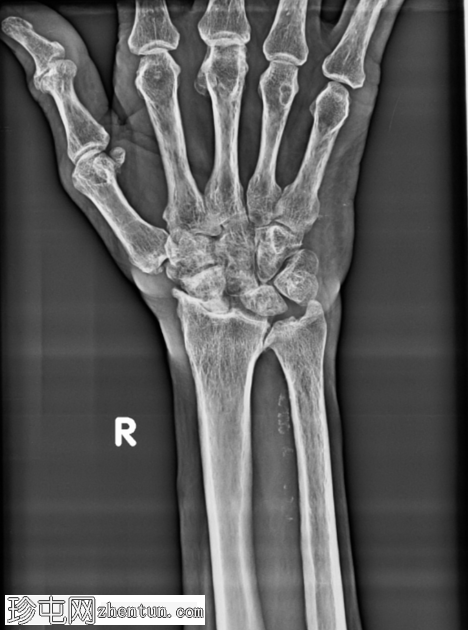

正位片

腕关节明显退行性改变,腕骨排列异常。舟月间隙增宽,符合舟月韧带功能不全的表现。头状骨近端移位。桡腕关节间隙明显狭窄,软骨下硬化,边缘骨赘形成。远端桡尺关节也可见退行性改变。腕骨、桡骨远端和尺骨均可见骨质疏松。未见急性骨折或脱位。